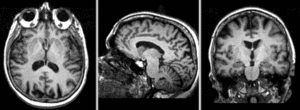

Registration Results

Exam 1 co-registered Exam 1 co-registered: FLAIR and T2 aligned with T1

Exam 2 co-registered Exam 1 co-registered: FLAIR and T2 aligned with T1